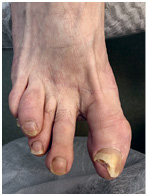

Другой пример – вальгусная деформация стопы, или известная всем выпирающая косточка. Подолог расскажет такому пациенту, какую обувь носить, чтобы избежать развития проблемы, наложит тейп, который предотвратит рост шишки. Но на операцию по удалению пациент пойдет к хирургу.

На этом снимке отчетливо виден экзостоз